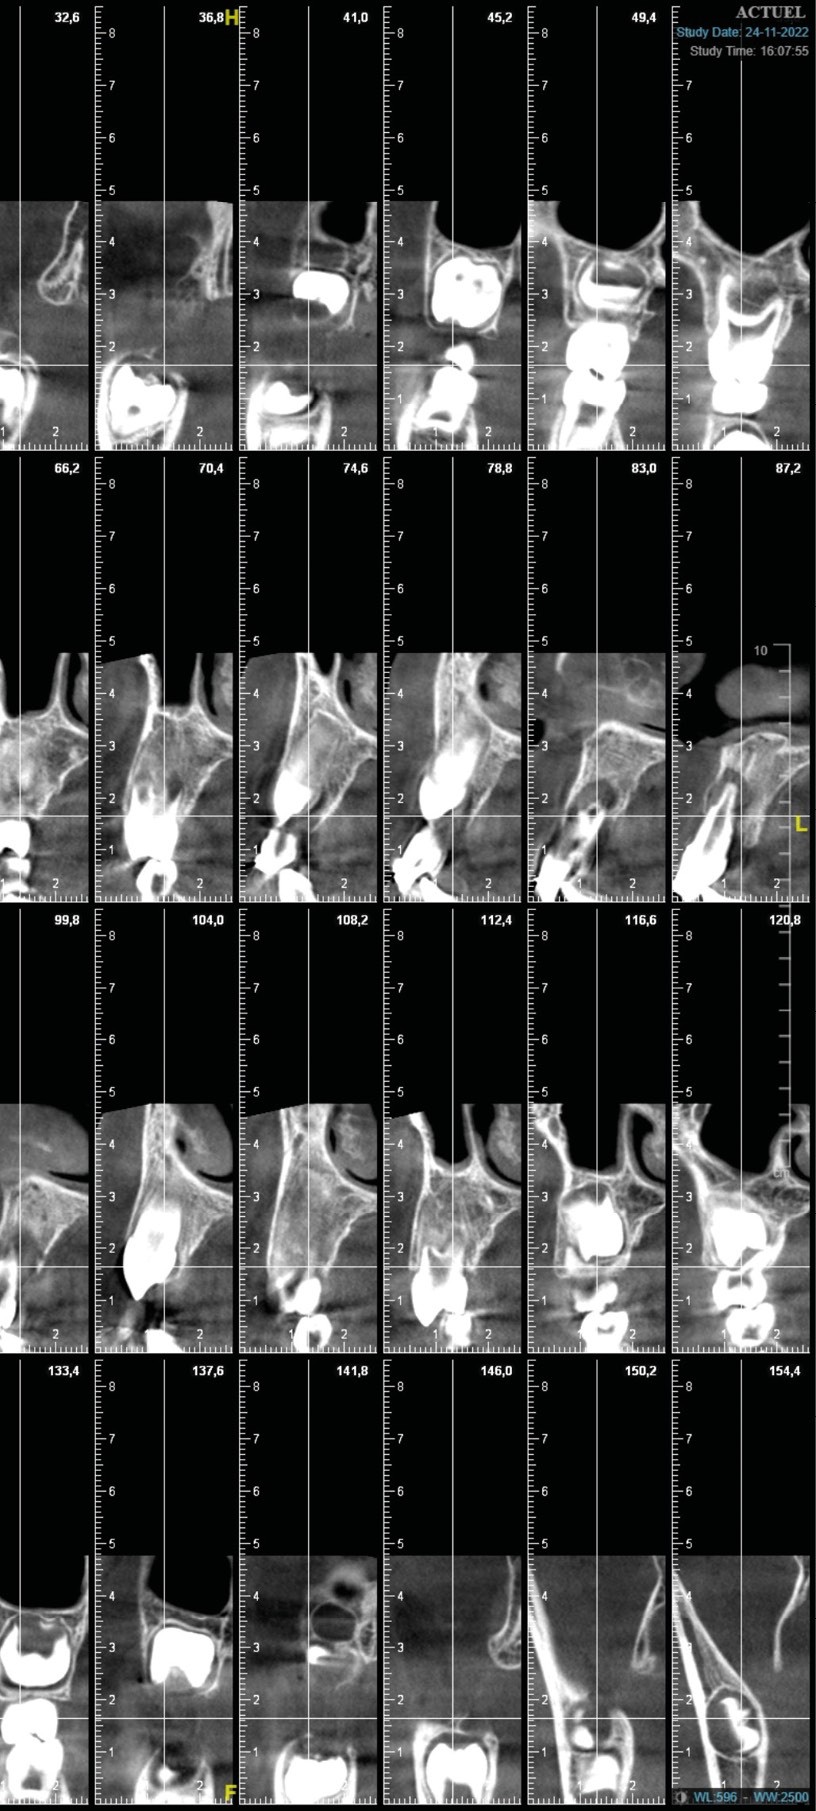

Faute de suivi, aucune prise en charge endodontique n’avait été entreprise dans les jours suivant le traumatisme. Du fait de la mobilité importante des incisives maxillaires, la contention a été laissée en place. Une radiographie panoramique et un cone beam ont également été réalisés. Ces derniers montrent une résorption radiculaire externe des dents 12-11-21-22 (fig. 1a-c).